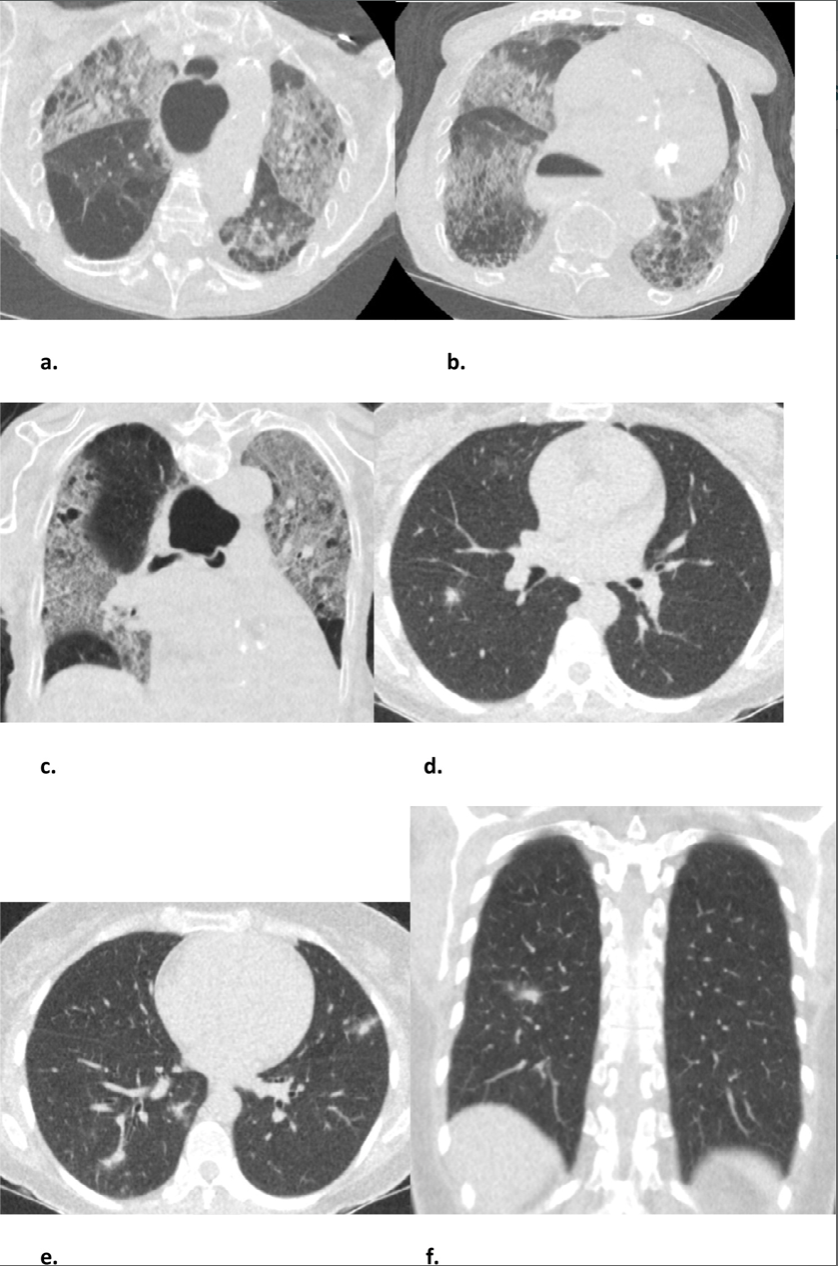

9/25 ct scan covid- In the early stage of the disease (Stage1), CT scans showed in 34 % lesions that involved a single lung lobe and in 212 % no lung involvement (Table 2) The most frequent CT findings of COVID19 pneumonia were GGO, crazypaving pattern, consolidation and linear opacities (Figs 1, 2) The predominant patterns of abnormality changed over timeGlobally, the accepted cutoff for Ct value for Covid19 ranges between 35 and 40, depending on instructions from the respective manufacturers of testing equipment The ICMR has arrived at the Ct value of 35 based on laboratory experiences and inputs taken from several virology labs

Chest Ct Severity Score An Imaging Tool For Assessing Severe Covid 19 Radiology Cardiothoracic Imaging

Mean age 632 ± 158, range 27–90 years) with a positive RTPCR test for SARSCoV2 Apart from CORADS, HRCT scans also seldom mention CT severity score, which tells us about the actual lung involvement due to the infectionObjectives To correlate a CTbased semiquantitative score of pulmonary involvement in COVID19 pneumonia with clinical staging of disease and laboratory findings We also aimed to investigate whether CT findings may be predictive of patients' outcome Methods From March 6 to , 130 symptomatic SARSCoV2 patients were enrolled for this singlecenter analysis and